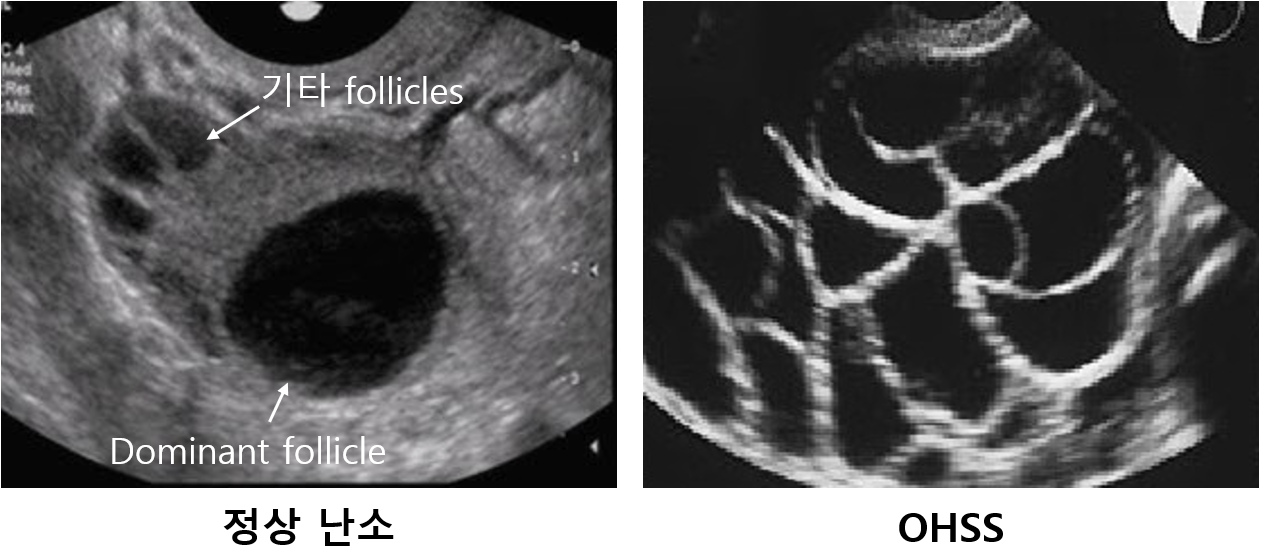

② 영상검사: US - 난소의 다발성 난포 크기 증가